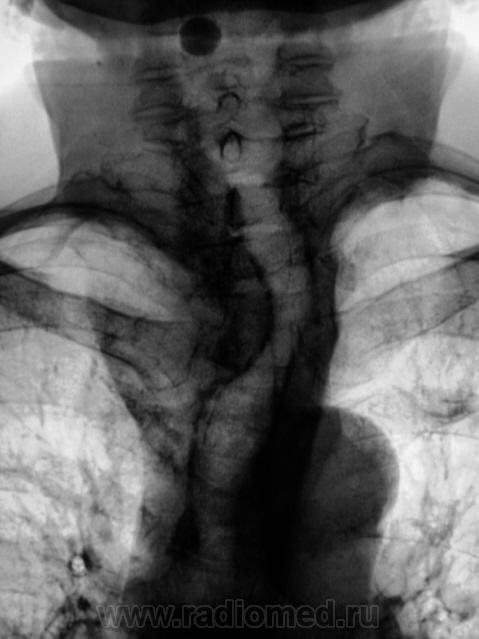

Экспансивно растущее об"емное образование верхнего средостения, неоднородной структуры за счет включений кальция. Состоит ли на учете у эндокринолога? Похоже на "ныряющий" зоб.

Думаю, что не "ныряющий", а конкретно "нырнувший", да там и "заночевавший" загрудинный зоб, включения кальция ничего хорошего не сулят. Согласен - УЗИ с, при необходимости,  биопсией.

Следует провести R-скопию, а желательно ещё и с рентген-контрастным веществом.